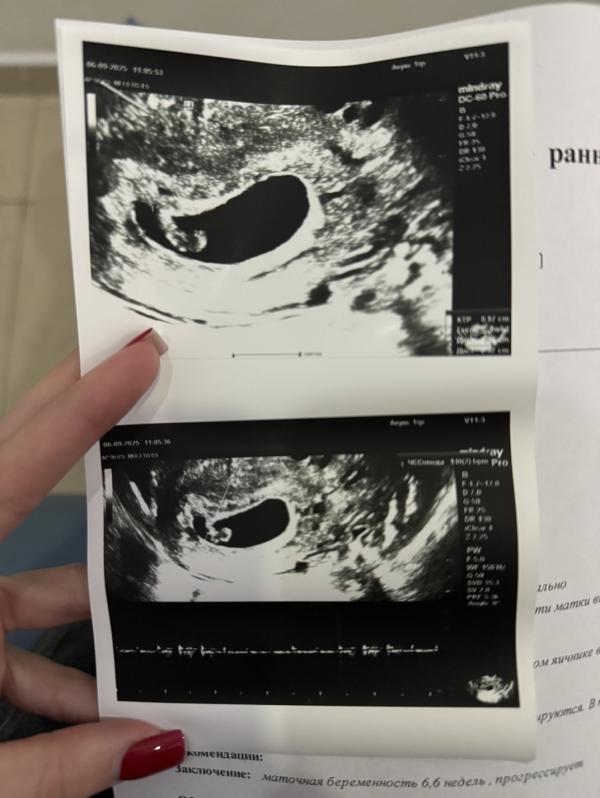

Я переживала, но вроде все хорошо. Сходила на 2 узи в 6.6 получается. Сказала становиться на учёт, а то я бледная, что-то с гемоглобином думает. Конечно, от всего тошнит. А запись в поликлинику только через 2 недели 🥲 Ну ладно, ждём